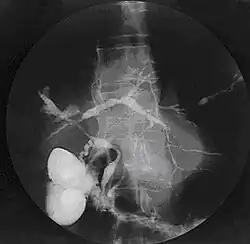

Cholangiographie d'une cholangite sclérosante primitive.

La mise en évidence d’anomalies des voies biliaires reste un élément clé du diagnostic malgré l’existence de formes particulières. L’examen classique de référence est l’opacification des voies biliaires, le plus souvent par cathétérisme rétrograde. Cet examen est techniquement difficile et a une morbidité certaine notamment en termes d’angiocholite (infection des voies biliaires). Il est désormais possible de visualiser les voies biliaires par un examen non invasif, la cholangio IRM (ou bili IRM) qui a une bonne sensibilité et spécificité[9]. La cholangio IRM tend donc à devenir l’examen de premier intention, le cathétérisme rétrograde n’étant pratiqué qu’en cas de difficulté diagnostique ou à visée thérapeutique. Les anomalies observées sont des sténoses souvent multiples, typiquement sans dilatation d’amont nette ; un aspect en chapelet est très évocateur ; des irrégularités murales, voire des aspects diverticulaires sont possibles. L’atteinte est le plus souvent intra- et extrahépatique, rarement uniquement intrahépatique (< 20 %) ou uniquement extrahépatique (< 10 %). Des atteintes du canal cystique et du canal pancréatique ont été rapportées.